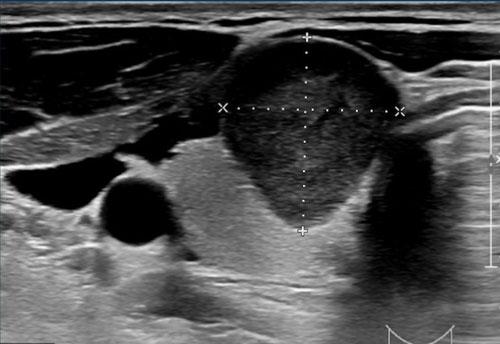

Nốt với Sự Phát Triển Ngoại Sinh

Nốt này cho thấy sự phát triển ngoại sinh với sự chèn ép các cấu trúc lân cận.

Tuy nhiên, không có bằng chứng rõ ràng về sự xâm lấn thực sự, và do đó, không đủ tiêu chuẩn để xác định là xâm lấn ngoài tuyến giáp.